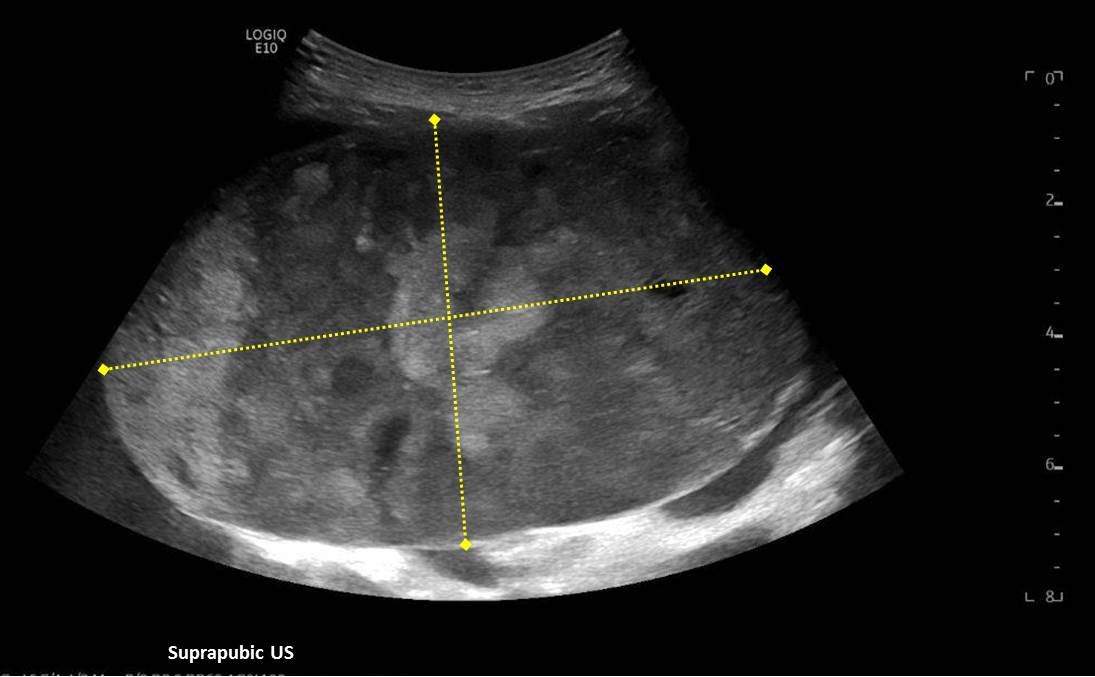

A 5-month-old female presented to the emergency department with worsening abdominal distention and postprandial emesis. Point-of-care ultrasound (POCUS) demonstrated extensive abdominal free fluid with a large, heterogeneous mass in the suprapubic region. This was confirmed on computed tomography (CT) of the abdomen and pelvis. The patient was urgently taken to the operating room for exploratory laparotomy where a ruptured tumor was discovered. The patient was eventually diagnosed with ovarian juvenile granulosa cell tumor. POCUS can be vital in guiding the recognition of rare pediatric conditions in the emergency department and should be considered in patients where there is concern for an acute abdomen.